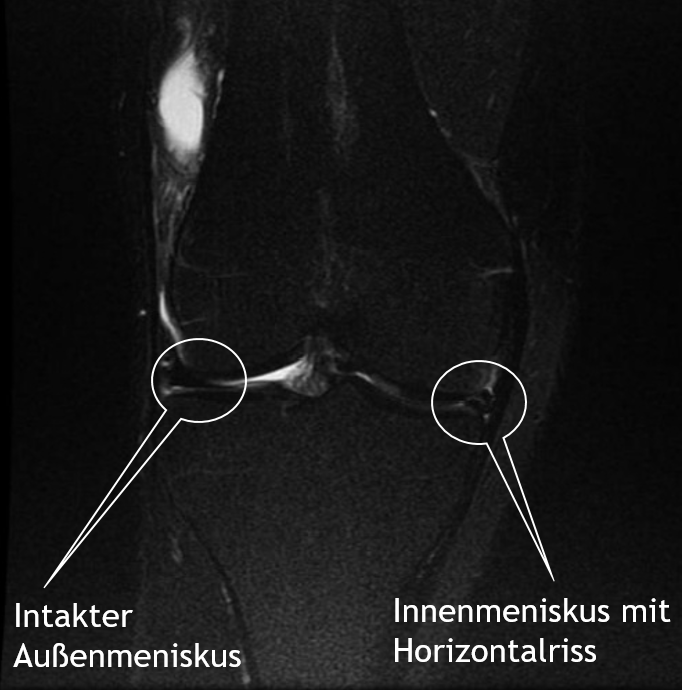

Diagnostik

Bei Verdacht auf eine Meniskusverletzung kann eine Magnetresonanztomographie (MRT) Klarheit schaffen. Dabei wird das  Weichteilgewebe des Knies, also die Bänder, Menisken und Muskeln, hochauflösend dargestellt. Anhand der Aufnahmen kann der behandelnde Arzt beurteilen, ob beziehungsweise welcher Teil des Meniskus Schmerzen verursacht.

intakter vs. gerissener Meniskus